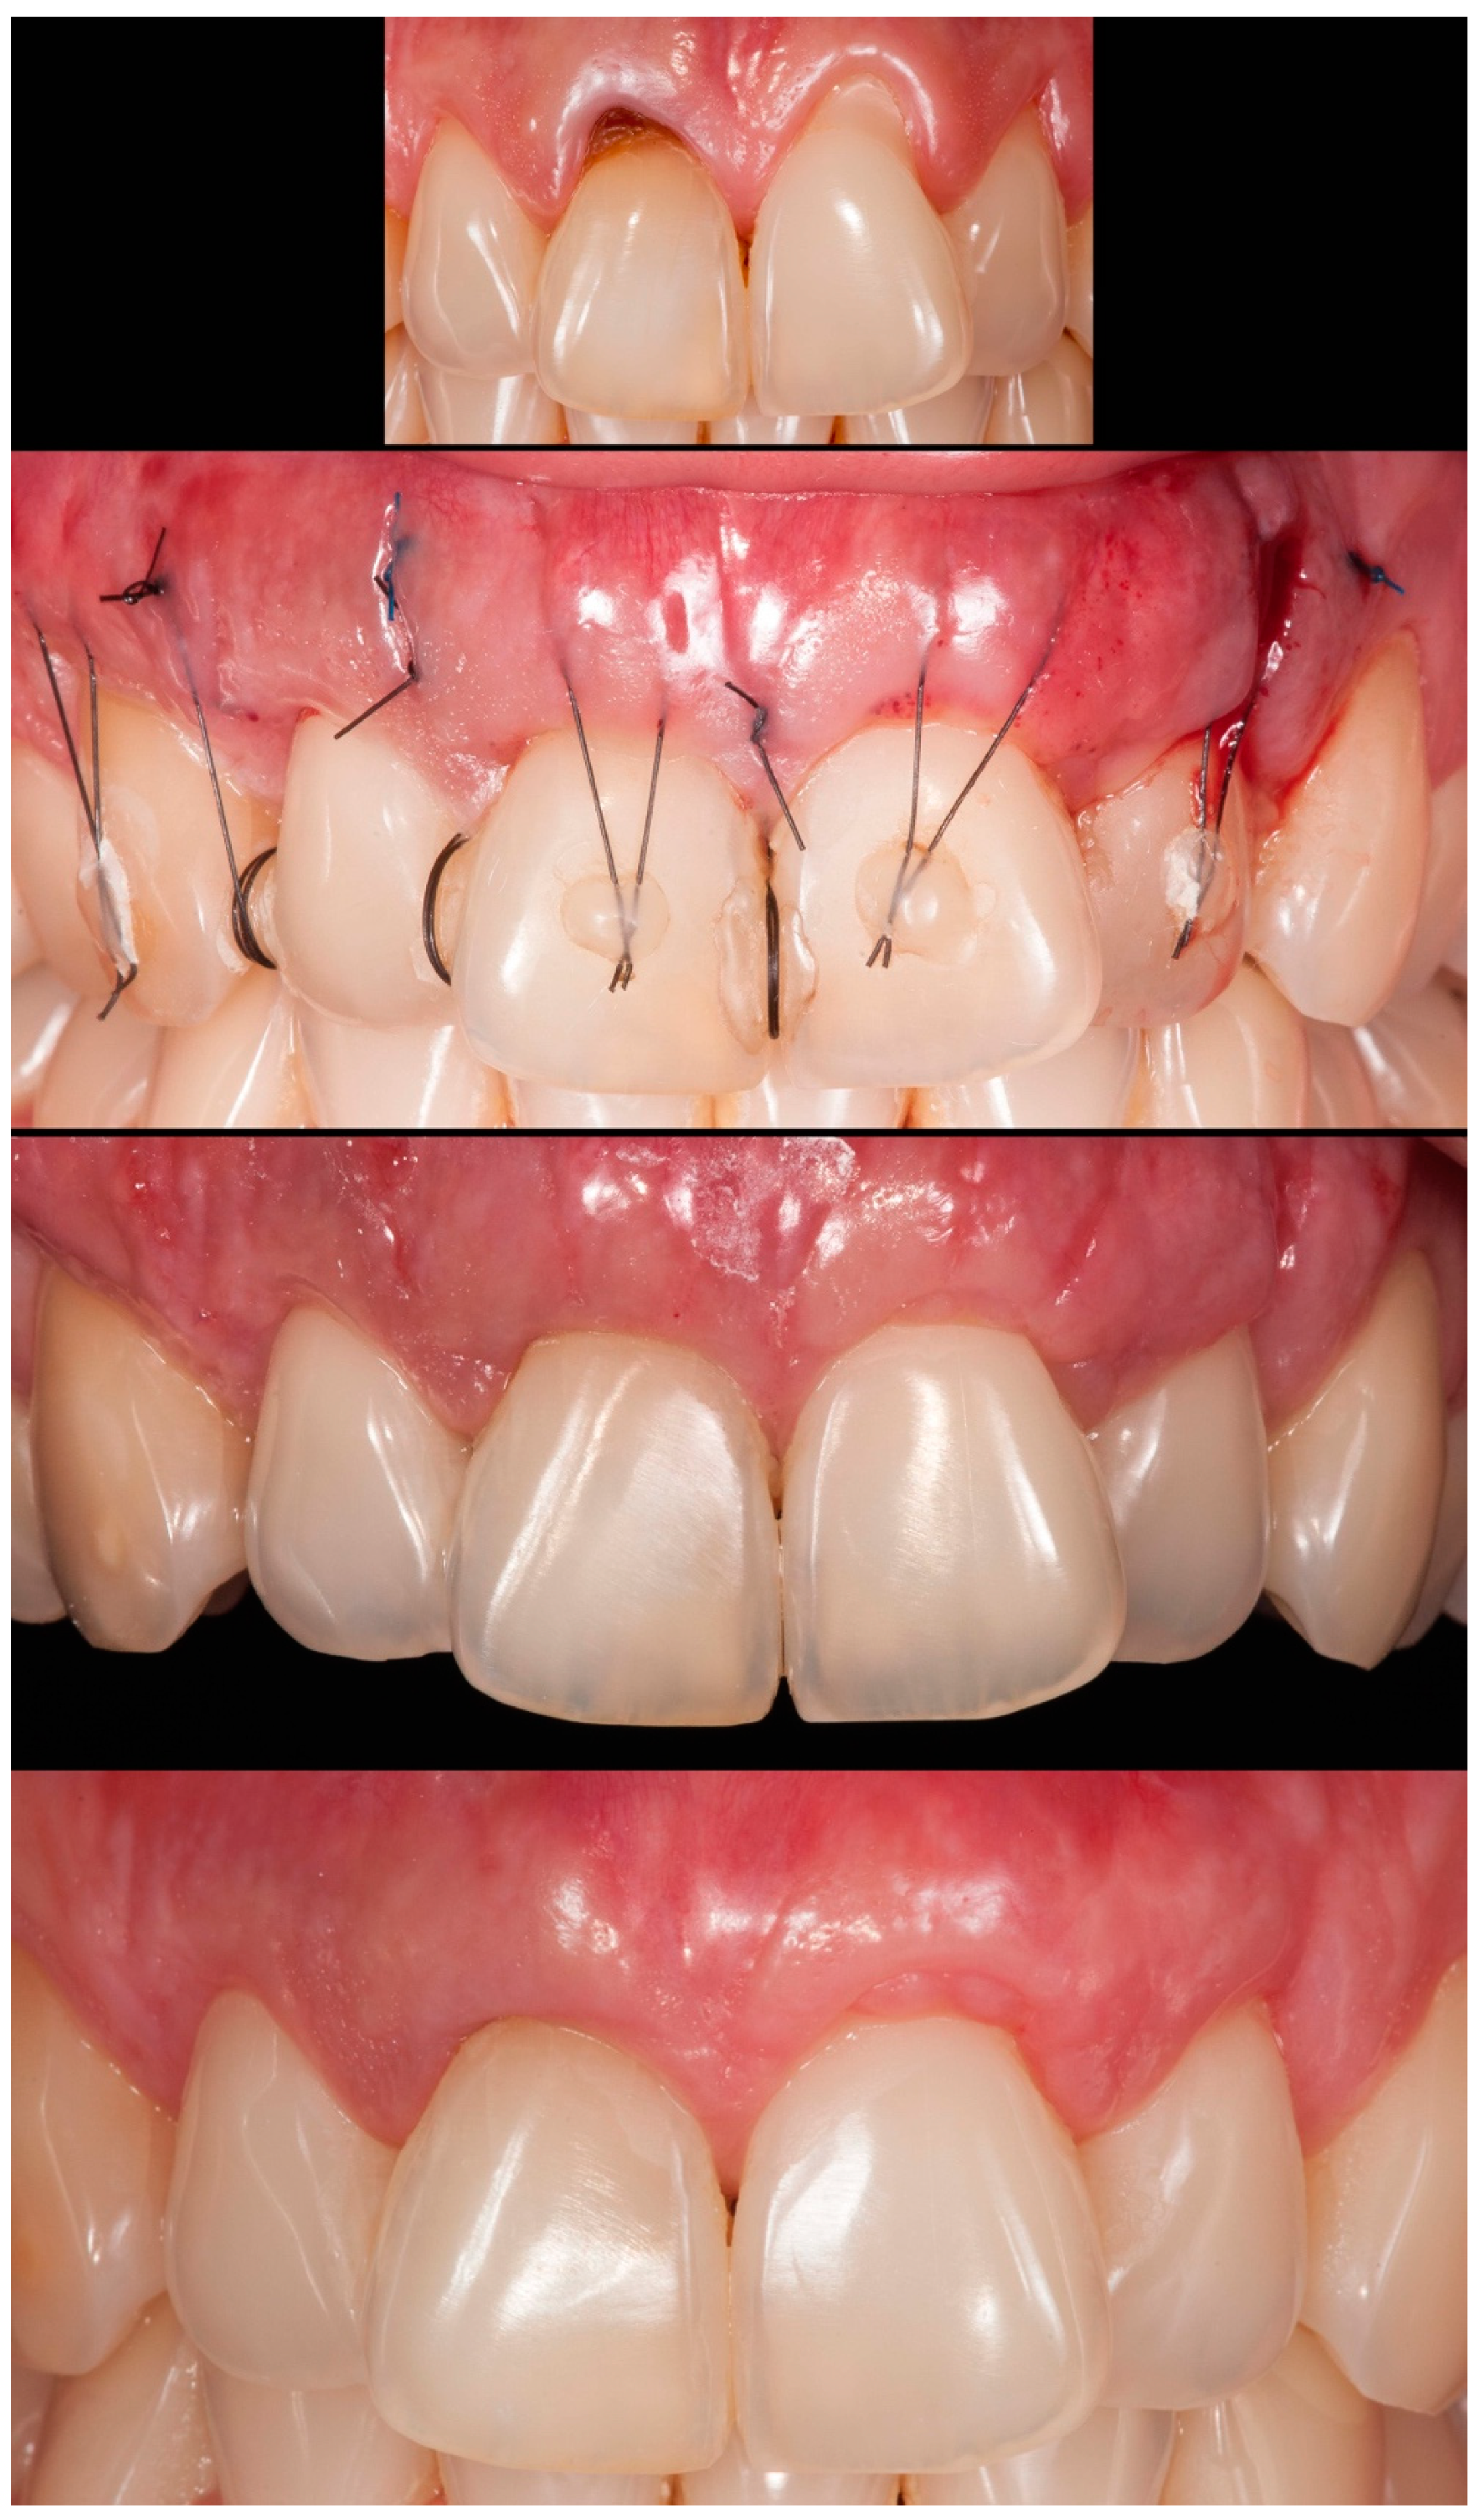

Case 1 was a male RT2 case involving tooth #41, with slight interproximal bone loss and gingival recession (GR) of 6mm (height) x 2.5mm (wide), which achieved the MGJ. No occlusal trauma was detected. The patient reported the use of fixed orthodontic brackets in the past. The MiTT protocol was entirely followed, and the suture was done with a composite in the buccal face of the teeth for coronal positioning. The result was followed for 1 year, achieving 82.25% RC (

Figure 2). A similar case was done in a female but involving tooth #31 with 3mm of GR (RT1), presenting a thin gingival tissue. The patient was scheduled for stitches removal after 7 days and recalled for re-evaluation after 1, 6 months, and 1 year. The result was better than case 1, achieving 100% for RC and improving the tissue thickness (

Figure 3). Case 3 involved one tooth (#41 – RT1). The recession had 1mm, and the anterior region had a thin phenotype. In addition, due to the thin thickness of the soft tissue found, the goal was to improve the thickness and cover the root. After applying the MiTT technique with a central vertical incision in the mucosa and using a de-epithelized CTG, an augmented soft tissue thickness was found with a complete RC (100%) (

Figure 4).

Figure 2.

Case 1 shows initial pictures of the GR defect (#41); immediate post-operative; and the healing period of 1 month and 6 months.

Figure 3.

Case 2 shows initial pictures of the GR defect (#31); and the healing period after 1 month and 1 year.

Figure 4.

Case 3 shows initial pictures of the GR defect (#41) and thin phenotype present; CTG over the receptor site and one vertical incision to apply MiTT; and the healing period after 6 months.